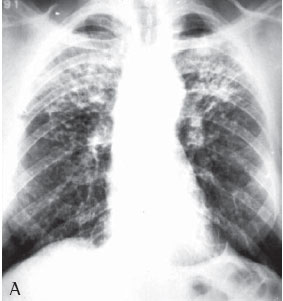

Quanto à classificação radiológica das grandes opacidades na radiografia de tórax verificou-se que: 23 pacientes apresentaram grande opacidade do tipo A (30,7%), 25 do tipo B (33,3%) e 27 do tipo C (36%) (Figuras 1A e 1B). Dos casos analisados, 74 apresentaram massas conglomeradas bilaterais, e apenas 1 apresentou lesão unilateral (Figuras 2A e 2B).

De todos os casos analisados (n = 75), apenas um apresentou grande opacidade unilateral simulando massa tumoral, sendo o diagnóstico de silicose feito através de toracotomia com biópsia pulmonar a céu aberto. Lesões solitárias de FMP são freqüentemente confundidas com câncer de pulmão. Considerando-se a maior incidência de câncer de pulmão nesses pacientes, é importante fazer uma abordagem diagnóstica para efetivamente diferenciar as lesões malignas das lesões benignas pneumoconióticas.(19)